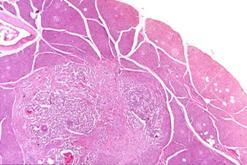

Los insulinomas son tumores generalmente benignos de las células excretoras de insulina del páncreas. Afecta a las células beta del páncreas, encargadas de la producción de insulina que el organismo necesita para el metabolismo de la glucosa. Habitualmente son tumores que afectan con mayor frecuencia al sexo femenino y cuyas edades oscilan entre los 40 y 50 años.

Los insulinomas son tumores poco comunes que se presentan en aproximadamente 1 de cada 250.000 personas. Estos ocurren usualmente como tumores únicos y pequeños en los adultos, del 5 al 10% de los insulinomas son malignos.